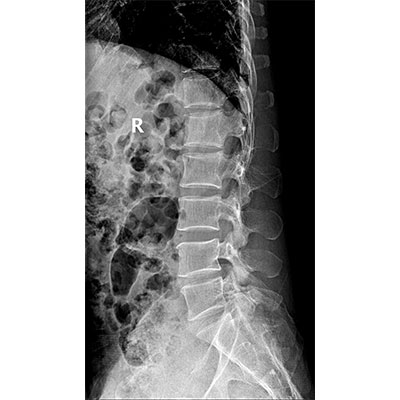

● 采用自主研發(fā)的技術(shù),在保證優(yōu)質(zhì)圖像的前提下,大大降低X射線劑量,用心呵護醫(yī)護工作者及患者的健康。

● 短曝光時間,便于老年人、兒童、殘疾人進行臨床拍攝。避免這類群體因不能有效控制身體運動等因素造成的運動偽影,提高攝片質(zhì)量及效率。